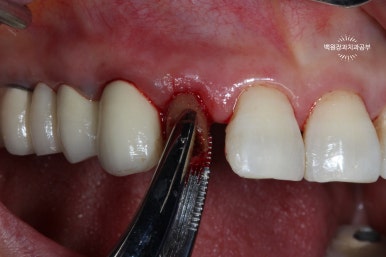

약 10일 정도 지나면, 봉합사를 제거합니다.

치아가 아직 흔들흔들 합니다.

약 10일 정도 지나면 실밥을 제거 할 수 있어요. 저희는 봉합사 제거라고 부릅니다. ㅎㅎㅎ

10일 정도 지나면 아직 치아가 흔들흔들 하긴 합니다.

약 한달 정도는 기다리셔야 합니다.

기다리는 동안 임시치아 만들어 드립니다.

앞니니깐 일단 급한대로 임시치아를 만들어 드렸습니다.

앞에서 보았을 때 어느정도 커버만 되면 되기 때문에, 보시다시피 얇은 레진치아를 사용하여 양 옆에 붙여드렸어요.

그래도 생각보단 자연스러워서 한달 정도 조심히 쓰시면 충분히 괜찮습니다.